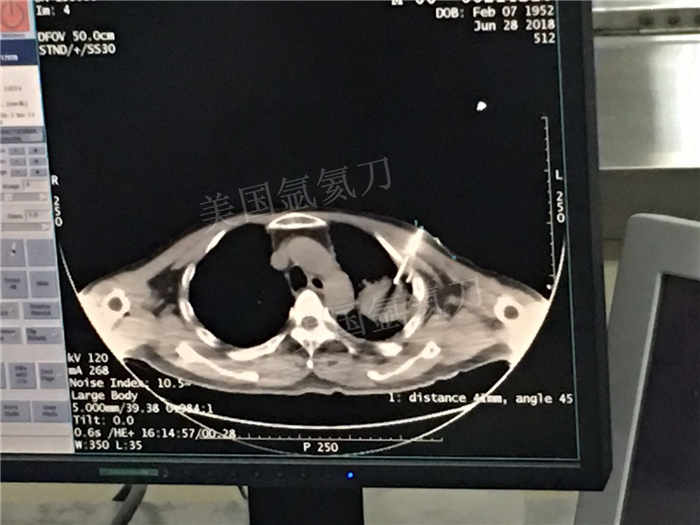

下一篇:中日友好医院氩氦刀冷冻消融治疗胸膜间皮瘤